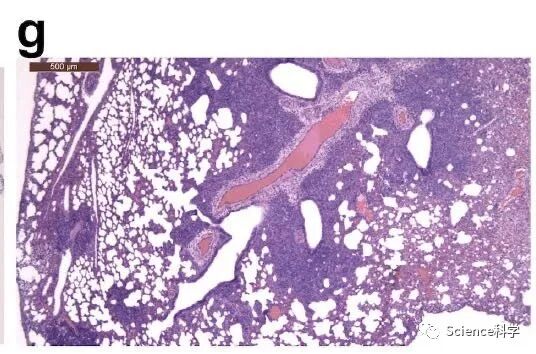

接种病毒后7天,30-60%的肺部实变,如下图所示:

但是,没有检测到病毒抗原如下图所示:

而2型肺细胞增生则很明显,如下图所示: